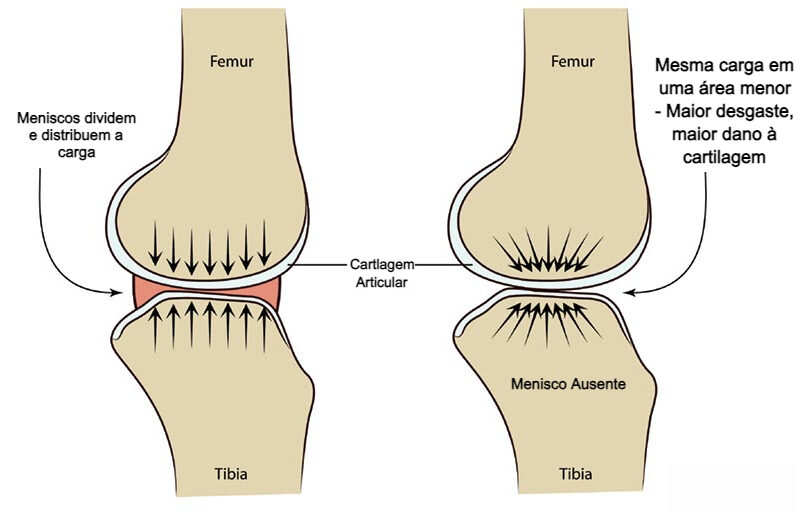

O joelho produz líquido sinovial para lubrificação e nutrição da articulação. Quando existe artrose, meniscopatia, sinovite ou outra alteração inflamatória, a produção de líquido pode aumentar. Parte desse líquido pode passar para a bursa gastrocnêmio-semimembranosa e ficar retido ali por um mecanismo semelhante a uma válvula de sentido único.

Esse fenômeno explica por que o cisto pode aumentar de tamanho ao longo do tempo, principalmente quando a doença de base não é tratada.

Cisto de Baker e lesão de menisco

Outra associação muito frequente é com a lesão de menisco, sobretudo lesões degenerativas. Nessas situações, a alteração intra-articular ajuda a manter o derrame e o fluxo de líquido para a região posterior do joelho, favorecendo a formação do cisto.